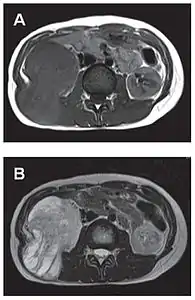

L'imagerie par résonance magnétique permet une exploration complémentaire dans certaines localisations. Elle est surtout réalisée pour les tumeurs du système nerveux central[8],[12],[43], du foie et du pelvis[31],[41]. Elle évalue mieux les différences de densité intra-tumorale et permet d'affirmer l'absence d'envahissement des tissus mous et des structures osseuses voisines[20]. Les tumeurs fibreuses solitaires ont un aspect d'isosignal en séquence T1 et d'hypersignal en T2, et se rehaussent après l'injection de gadolinium[31]. Cependant, dans le système nerveux central, elles ne présentent pas de critères caractéristiques permettant de poser un diagnostic de manière uniquement radiologique[12] et, en pré-opératoire, sont souvent confondues avec un méningiome[43].

- Tumeur fibreuse solitaire du rétropéritoine

Aspect tomodensitométrique, sans (A) puis avec (B) injection de produit de contraste[44].

Aspect IRM, en séquence T1 (A) et T2 (B)[44].